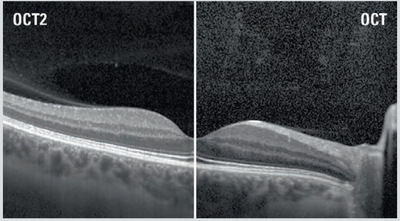

The DRI OCT Triton combines the world’s first Swept Source OCT technology with multimodal fundus imaging. Multimodal All-in-One fundus imaging tool will bring the next level of diagnostic capability to you and your patients.

Combining comprehensive aspects of swept-source OCT, Topcon’s DRI OCT Triton ensures high-quality imaging. It takes into account various aspects of imaging to ensure high-resolution fundus imaging, which in turn guarantees better-quality images for more accurate assessments. These are some key features of the DRI OCT Triton that make it an ideal choice for your practice.

The Topcon DRI OCT Triton is a multimodal swept-source OCT system equipped with a non-mydriatic color fundus camera. Utilizing a 1,050 nm wavelength light source, and a scanning speed of 100,000 A Scans/sec, it provides uniform scanning sensitivity allowing superior visualization of the vitreous and choroid in the same scan.

Invisible OCT scanning light, eye tracking during the capture of selected scans, along with high scanning speeds reduce the effect of patient eye movement, improving workflow and allowing for more data be to collected in a shorter period. A 12 mm x 9 mm widefield scan along with automated layer segmentation provides measurement and topographical maps, with reference database, of the optic nerve and macula in one scan.